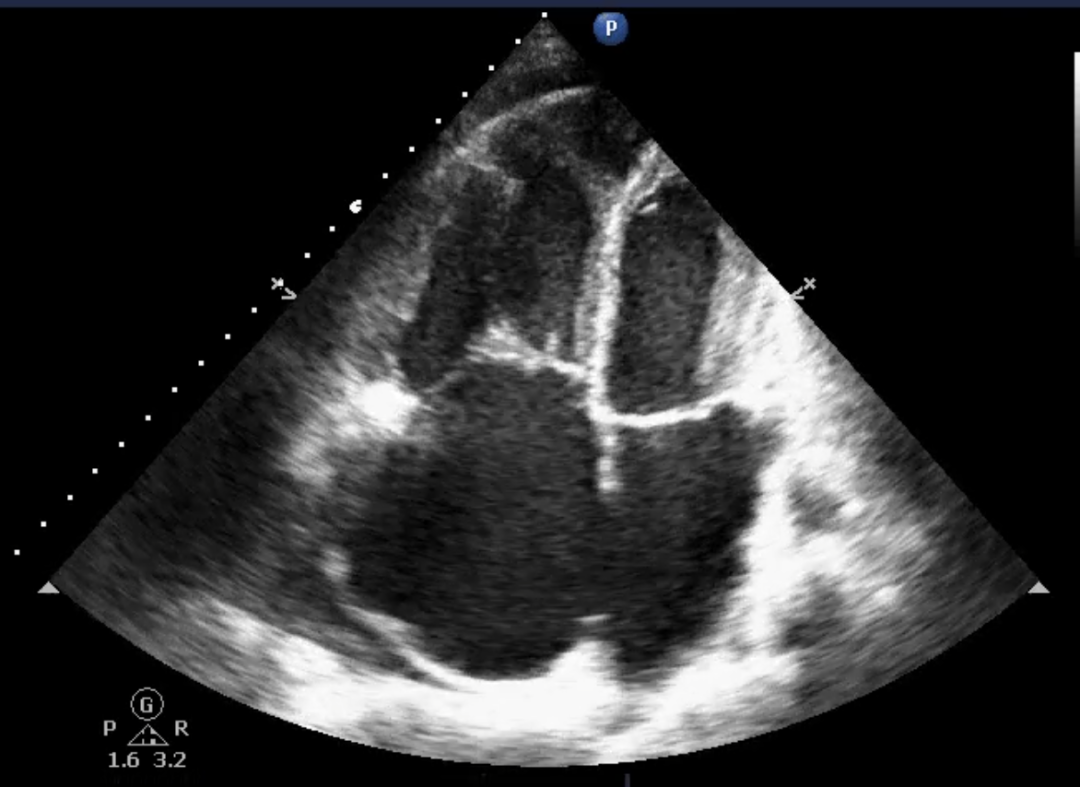

比如,我们面对的是一个肺栓塞的病人,表现为典型的肺心病(图 7 ),由于肺动脉高压、右心扩张等因素,下腔静脉表现为扩张固定。此时合并低血压,是因为左心室舒张末期容量不足,且被右心压迫( D 字征)导致舒张受限,左心室表现为「 收缩力正常,血容量不足 」的状态(因为血液都被肺动脉阻挡在右心了)。

此时,我们如果单纯根据下腔静脉扩张固定,就进行脱水的话,那么左心室舒张末期容量将进一步不足,血压可能继续下降,休克状态更加严重!

图 7 肺栓塞合并肺源性心脏病的超声表现

图片来源:作者提供